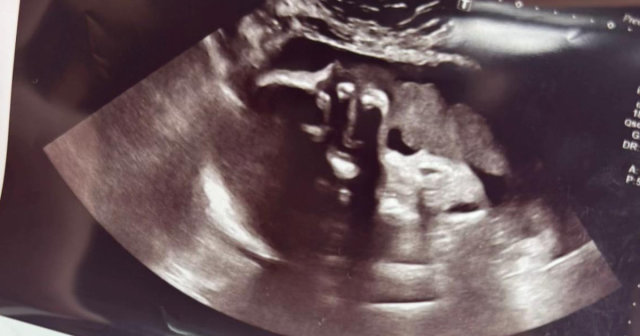

ママさんは次女ちゃんがおなかの中にいた当時、妊娠中の胸焼けがひどかったため、妊娠32週の検診の際に、エコー検査をする産科医に髪の毛が見えるかどうか質問しました。アメリカなどでは、赤ちゃんの髪の毛がふさふさだと妊娠中の胸焼けがひどくなるという迷信的な言い伝えがあり、もしかしたら……と聞いてみたようです。

すると産科医から、「少しだけ生えていて、あまり多くはないでしょう」といった言葉が返っていました。それからしばらくして無事に出産を終え、生まれたばかりの赤ちゃんを確認すると、頭皮は透けて見えていましたが、エコー検査時の予想よりは生えている印象でした。